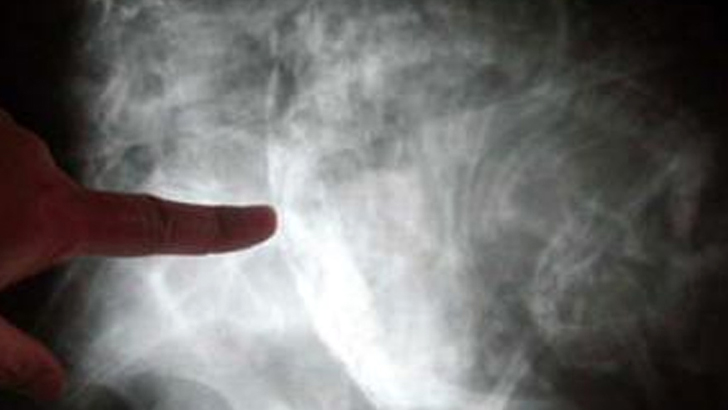

স্টোন বেবি। ছবি: আনন্দবাজার

কলোম্বিয়ার এক বৃদ্ধা পেটের কিছু সমস্যা নিয়ে হাসপাতালে ভর্তি হন। এক্স-রে রিপোর্ট দেখে হতবাক হয়ে যান তিনি। পরীক্ষা-নিরীক্ষায় তার পেটে ‘স্টোন বেবি’ (পাথুরে ভ্রূণ) ধরা পড়ে।  যাকে চিকিৎসাবিজ্ঞানের ভাষার বলা হয় ‘লিথোপেডিওন’।  খবর আনন্দবাজারের।

চিকিৎসকরা জানান, ওই বৃদ্ধার তলপেটের এক্স-রে করানো হলে তাতে ধরা পড়ে ‘লিথোপেডিওন’ হয়েছে তার।  চিকিৎসকদের পরিভাষায় যা অতি বিরল ঘটনা।  একে ‘স্টোন বেবি’ও বলেন তারা।